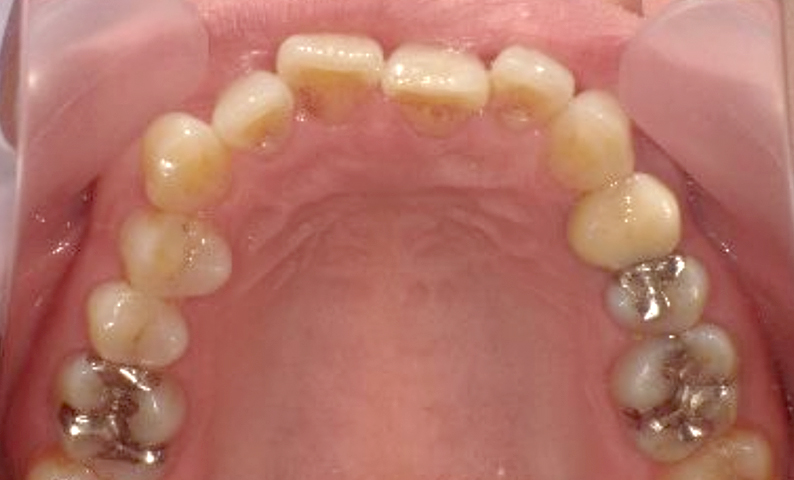

症例_002 上顎だけの部分矯正

治療期間:7ヶ月金額:30万円+税女性前歯のガタガタ上の前歯だけ

| Before | After |